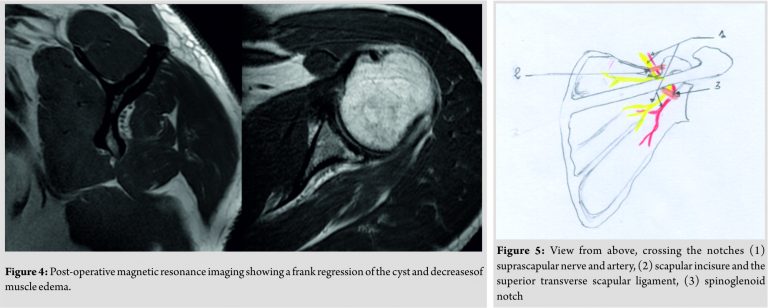

When testing the rotator cuff, Patte test and palm-up test were both positive, and there was no subacromial impingement process. Standard X-rays of the shoulder were normal. Magnetic resonance imaging (MRI) revealed a posterior spinoglenoid notch cyst, associated with an important edema of the infraspinatus muscle (Fig. 2 and 3). Given this cystic aspect which led to compression of the suprascapular nerve as well as the muscular atrophy of the infraspinatus, non-operative treatment including percutaneous needle aspiration and intralesional steroid injection was considered no longer effective. We opted for arthroscopic surgical resection. During the arthroscopic procedure, a labral lesion type SLAP II was identified and repaired with suture anchors. The cyst was evacuated allowing suprascapular nerve decompression. The operative follow-up was simple. At 1-year follow-up, the patient did not show any more pain, with a total recovery of muscle strength. Constant shoulder score was95, and a shoulder MRI done9months postoperatively showed a frank regression of the cyst and decrease of muscle edema (Fig. 4).

The suprascapular nerve originates from the brachial plexus (C4-C5-C6) and is essentially a motor nerve. It innervates the supra- and infra-spinatus muscles. It does not have a sensitive cutaneous territory. It is located about 2 cm from the capsule and passes through the supraspinatus fossa. Its path presents two critical points of passage(Fig. 5) [2]. A superior passage in the scapular incision which is closed at the top by the very solid superior transverse scapular ligament. An inferior and posterior passage at the spinoglenoid notch where it can be constrained by the inferior transverse scapular ligament. The muscular involvement may vary according to the seat of compression of the suprascapular nerve. The supraspinatus muscle is affected by compression at the level of its upper portion and that of the infraspinatus at its posterior portion. The causes of compression are multiple; the most common is a lesion of the labrum resulting in the formation of a cyst. The physiopathology is applicable toparameniscalcysts: The increase in intra-articular pressure drives the latter through the labral lesion, which forms a cyst. This pathology is rare with a ratio of 2–4% in the general population. However, it is often underestimated and diagnosed at a late stage [5,6]. In our case, only the infraspinatus muscle was concerned given the location of the cyst. The upper portion of the suprascapular nerve relevant to the supraspinatus muscle did not suffer from compression by the cyst. In consequence, there was no clinical sign of supraspinatus involvement, therefore, a negativeJobb test. Ductal syndromes of the suprascapular nerve are often seen at the stage of chronic neuropathy[1,2,5]. The patient consults for atypical pain suggestive of cervicobrachial neuralgia or rotator cuff syndrome. The initial pain is often diurnal and nocturnal, to become secondarily mechanical. Clinical examination will essentially check for a decrease in external rotation muscle strength, as well as amyotrophy of the supraspinatus fossa by palpation and amyotrophy of the infraspinatus fossa which can be clearly visible [2,3,4]. MRI and arthro-MRI are currently considered as the reference examinations for the positive, topographical, and etiological diagnosis of suprascapular nerve entrapment[7]. They allow the diagnosis as well as evaluation of muscular denervation. The most common radiologic signs are edema, atrophy, and fatty degeneration. Muscular pain is initially manifested by the presence of edema, which is a sensitive and specific sign of muscular denervation. It is a T2 diffuse hypersignal, homogeneous and concerns all the muscle. The topography corresponds to the territory of the motor branch intended for supra- or infra-spinatus. TheT2 hypersignal of the infraspinatus muscle was very visible on MRI sections in our patient (Fig. 2 and 3). Muscular atrophy and fatty degeneration become visible in chronic cases with a long evolution[5,8]. Arthro-MRI highlights its articular origin by seeking a lesion of the labrum. Computed tomography (CT) arthrography is often negative, and only the indirect sign of fat disappearing from the spinoglenoid indentation can suggest the diagnosis [7]. Nerve conductionstudies maybe helpful in confirming the diagnosis and have a greatprognostic value by giving information on the severity of the lesions. The non-operative treatment options are varied and include oral medications including nonsteroidal anti-inflammatory drugs as well as percutaneous needle aspiration associated with intralesional steroid injection. However, symptomatic paralabral cysts causing muscular atrophy that fails to respond to conservative treatment should be treated surgically. Several studies shown high prevalence of labral tears in connection with spinoglenoid cysts and have suggested a high recurrence rate if the intra-articular labral pathologic process is not addressed [1,5,6]. Schroder[6] objectified a recurrence rate close to 0% after labral repair. Hence, surgical treatment should not be limited to the resection of the cyst, but the labral lesion must be repaired to prevent recurrence[5,6,9,10].